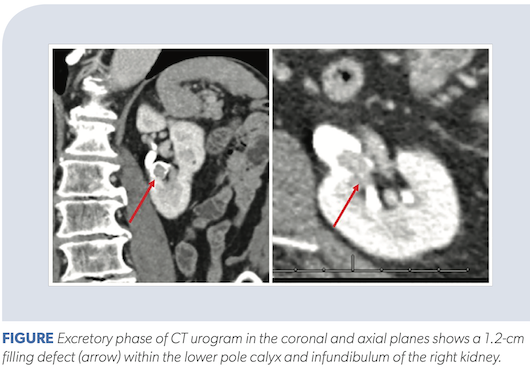

Bladder Cancer Detection With Ct Urography In An Academic Medical Center Radiology